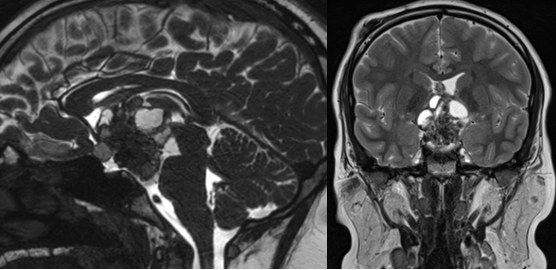

视力模糊、剧烈头痛,14岁的小K从未想过会查出颅咽管瘤。肿瘤位于视交叉后方,而且出现明显的钙化,这也是颅咽管瘤的显著特征。

小K父母找到INC另一位儿童神经外科大咖鲁特卡教授。教授先进行VP分流术缓解脑积水。鲁特卡教授认还通过内镜经鼻入路为小K手术,不开颅顺利全切了肿瘤。

术后,小K的视力得到改善。这是小K的第一次手术,全切是良好预后的基础,他至今未复发。